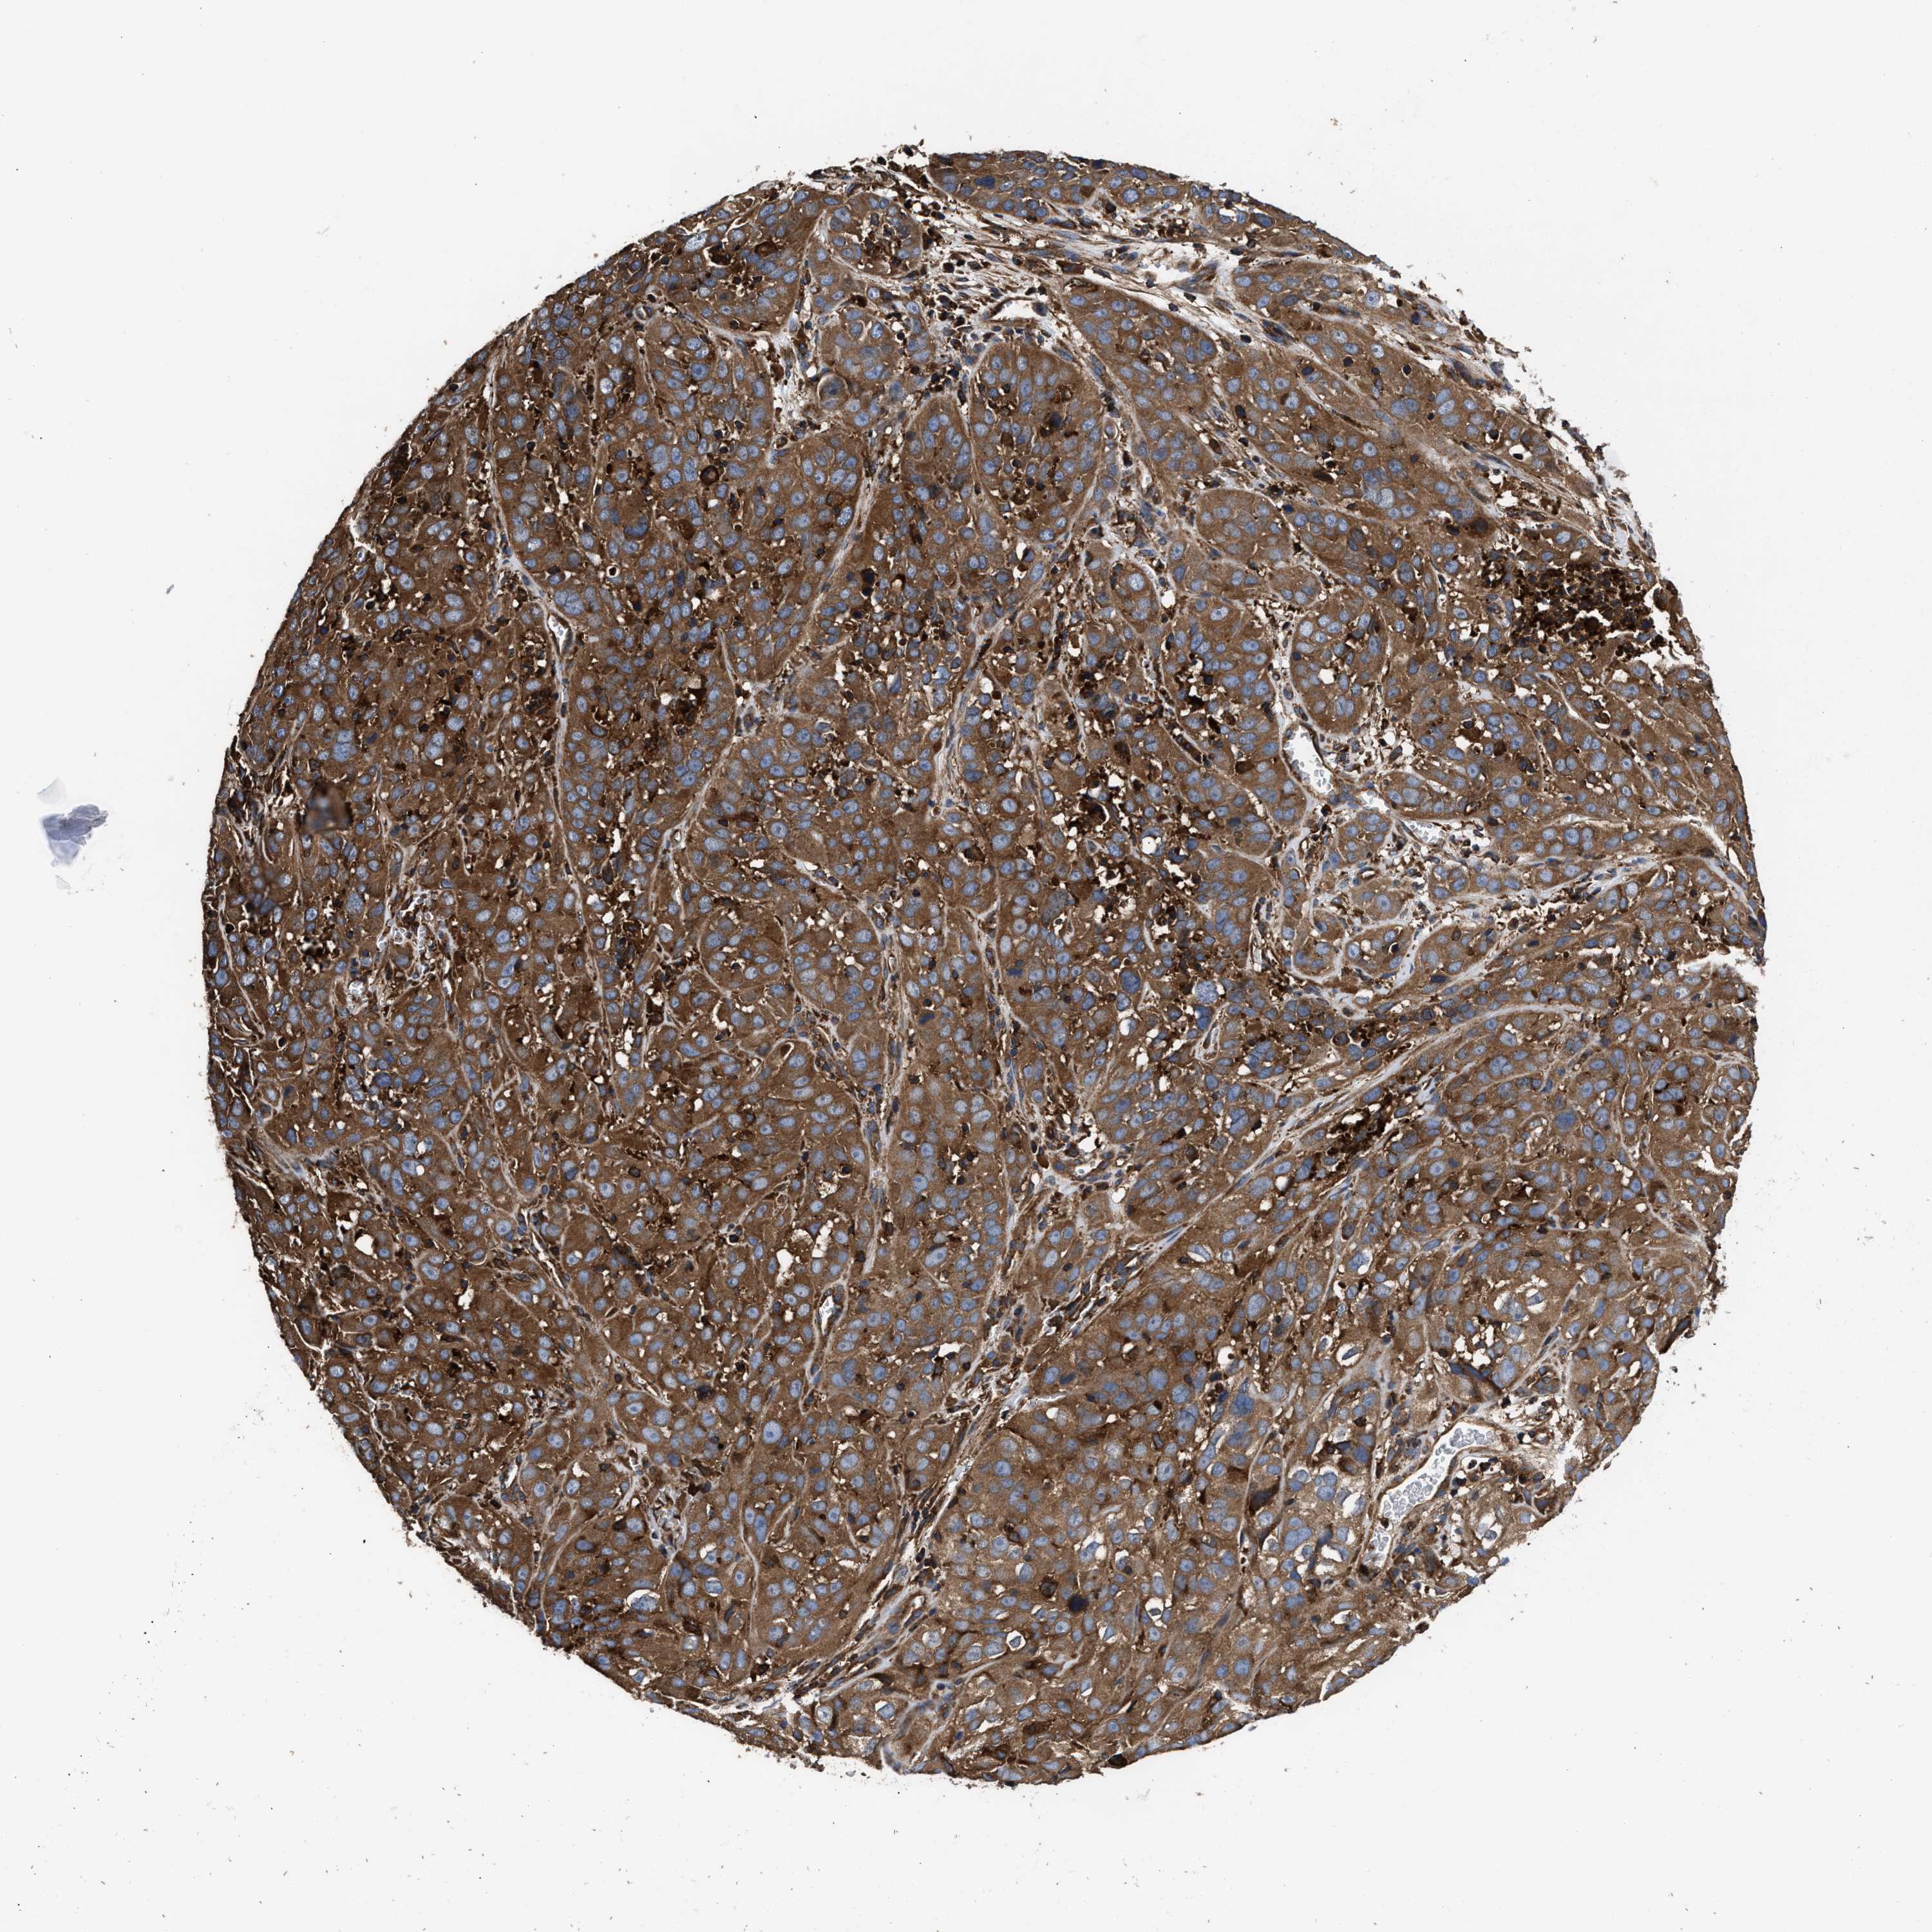

CERVICAL CANCER - Protein expressioni

A mouse-over function shows sample information and annotation data. Click on an image to view it in a full screen mode. Samples can be filtered based on level of antibody staining by selecting one or several of the following categories: high, medium, low and not detected. The assay and annotation is described here.

Note that samples used for immunohistochemistry by the Human Protein Atlas do not correspond to samples in the TCGA dataset.

Antibody stainingi

Antibody staining in the annotated cell types in the current human tissue is reported as not detected, low, medium, or high, based on conventional immunohistochemistry profiling in selected tissues. This score is based on the combination of the staining intensity and fraction of stained cells.

Each image is clickable and will lead to virtual microscopy that enables deeper exploration of all samples and also displays staining intensity scores, fraction scores and subcellular localization as well as patient and tissue information for each sample.

Antibody HPA021176

Antibody HPA021177

Antibody HPA027736

Squamous cell carcinoma, NOS

Adenocarcinoma, NOS